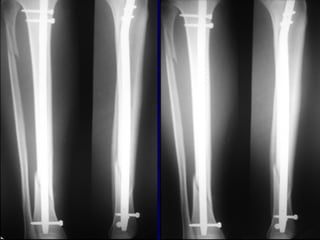

Expanded Indications • Proximal1/3 • Distal 1/3 • Increased Problems

• 53.

• Proximal Fractruesare technically more challenging • Prone to Valgus & • Pro-curvatum deformities

Technique • Screws placedon concave side of deformity.

Blocking (Poller) Screws •Functionally narrow im canal • Increase strength and rigidity of fixation

The Use ofPoller Screws as Blocking Screws in Stabilising Tibial Fractures Treated with Small Diameter Nails • 21 patients • All healed within 3-12 months • Mean alignment 1 degree valgus, antecurvatum 2 degrees. Krettek C, et al. JBJS 81B: 963, 1999

Reduction of DistalTibial Fractures • Distractor • Joy Stick • Fibular Plating • Calcaneal Traction

Proximal and DistalCases Courtesy of R. Winquist M.D. Seattle, Wa.